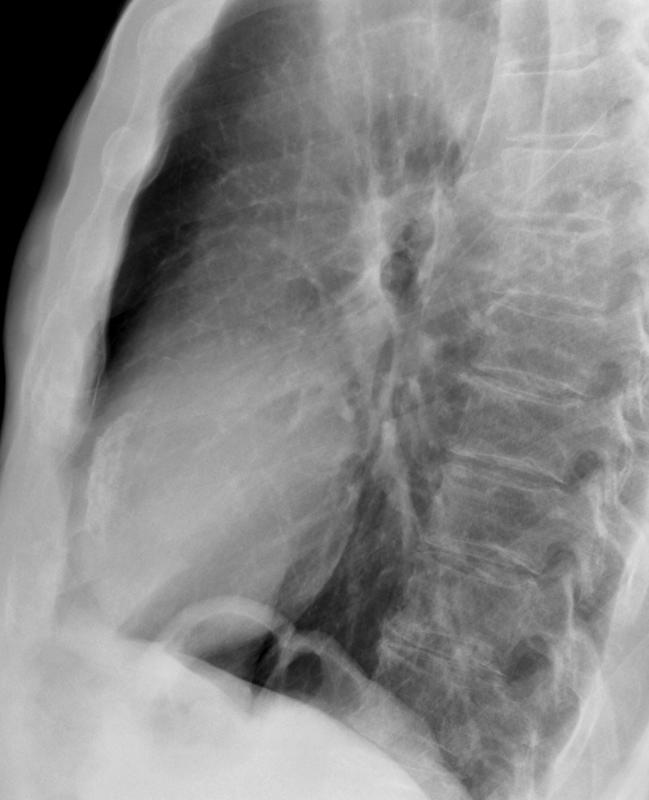

Gallery Cardiac Other LV ant wall calcif (can't see on PA)

LV ant wall calcif

(can't see on PA)